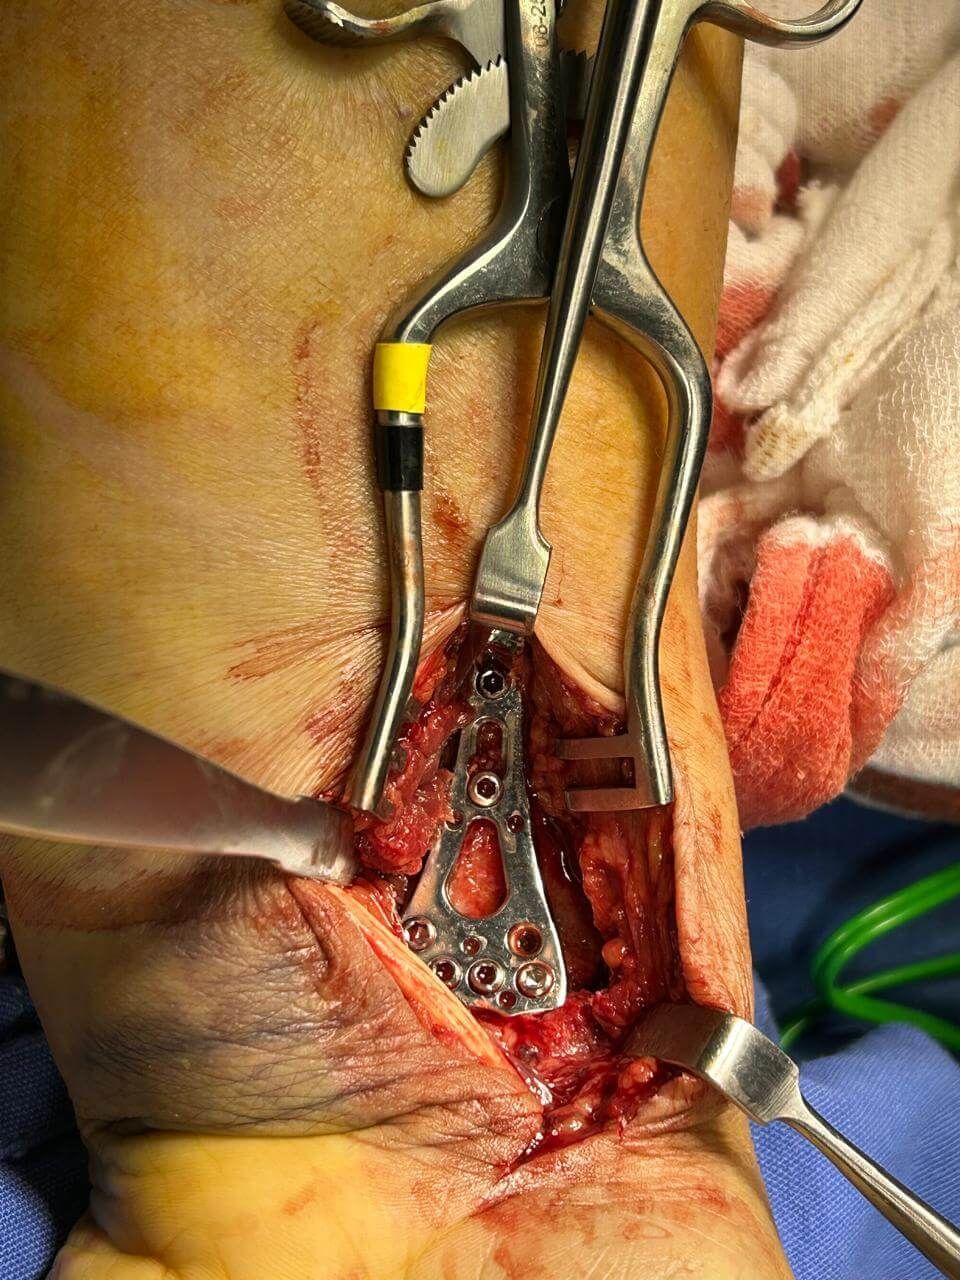

Cirugía de pie con mínima invasión

Enfocado en abordajes menos invasivos para tratar afecciones del pie.

Tratamiento de lesiones:

- Fracturas

- Luxaciones

- Esguinces

- Rotura de ligamentos